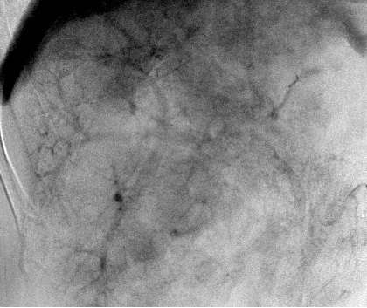

75  岁 肝转移癌 T/N Particle deposition

T/N Ratio 2.8